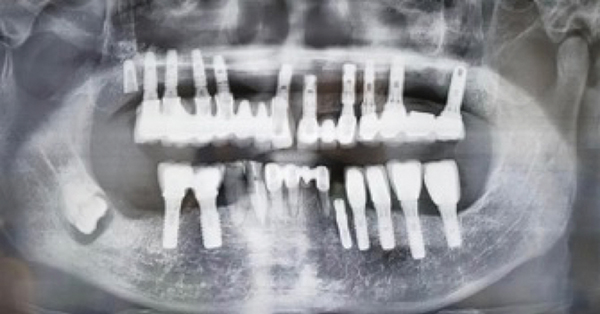

September 11 2013 by Ramsey Amin. Dizziness is a rare complication that can occur in patients that have an. When placing dental implants some dentists still rely on panoramic x-rays.

Ad See Why Over 145000 Patients Have Chosen ClearChoice Dental Implants. Ad Tooth implants procedure Near Me. A good implant dentist will make sure you get a CT scan before he plans the surgical placement.

These are 3D x-rays and help ensure the dentist gives proper. Can Dental Implant Cause Sinus Problems. More often then not one to two millimetres of an implant can penetrate the sinus cavity during placement of the implant.

The best practice is to use CT scans. They help replace tooth loss create a healthy smile and can overall improve speech and. Check If You Are Eligible for 0 Cost Dental Benefits.